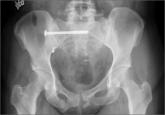

The Role of Computed Tomography for Postoperative Evaluation of Percutaneous Sacroiliac Screw Fixation and Description of a “Safe Zone”